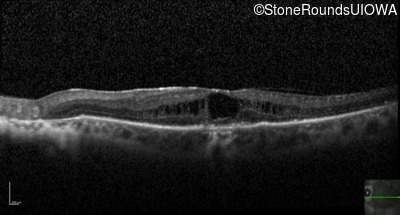

Optical Coherence Tomography - Left - 20/125 +2

Exemplar / OCT Stack

OCT Stack